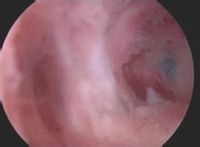

宮腔鏡下的宮腔積膿急性或慢性子宮內膜炎所導致的宮頸阻塞,如宮腔內的炎性分泌物不能外流或引流不暢,即可形成宮腔積膿。

1、子宮腔鏡檢查可了解有無宮腔積膿,並確定粘連部位、範圍、程度及粘連的組織。各組粘連的特點為:子宮內宮腔積膿與周圍的內膜很相似;肌纖維粘連最常見,其特點為有一薄層子宮內膜覆在上面,表面有很多腺體開口;而結締組織粘連則表面無內膜形成。